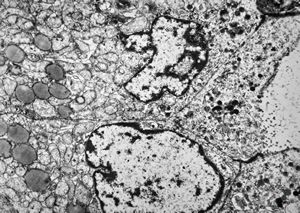

F, 72y. | carcinoid … metastasis to lymphonode